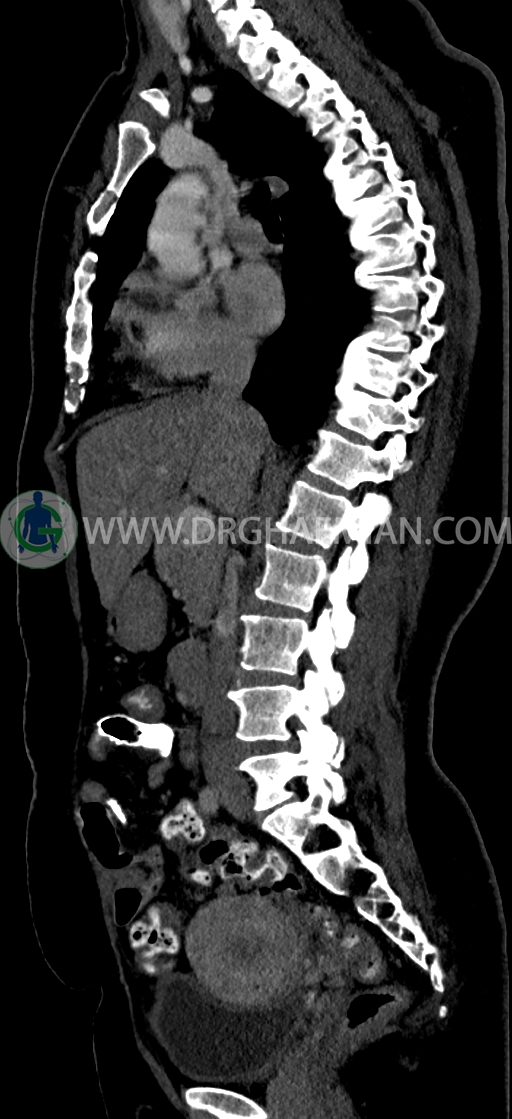

سی تی اسکن شکم و لگن یکی از روش های تصویربرداری با سی تی اسکن است. این روش با استفاده از اشعات ایکس تصاویر عرضی از ناحیه شکمی و لگنی ایجاد میکند. در این کیس سی تی اسکن هیپراستوز اسکلتی ایدیوپاتیک منتشر (DISH)، فیبروم اینترامورال، هرنی سوپرا امیلیکال دیده می شود.

در سي تي اسکن اسپيرال ريه و مدياستن-شکم و لگن با کنتراست خوراکی و وريدی (مولتي ديدکتور 16 با مقاطع ظريف و بازسازي هاي ساژيتال و کرونال) :

–Bridging osteophyte در مهره هاي توراسيک مطرح کننده DISH همراه با کيفوز مشهود است.

–lumbosacral transitional vertebrae